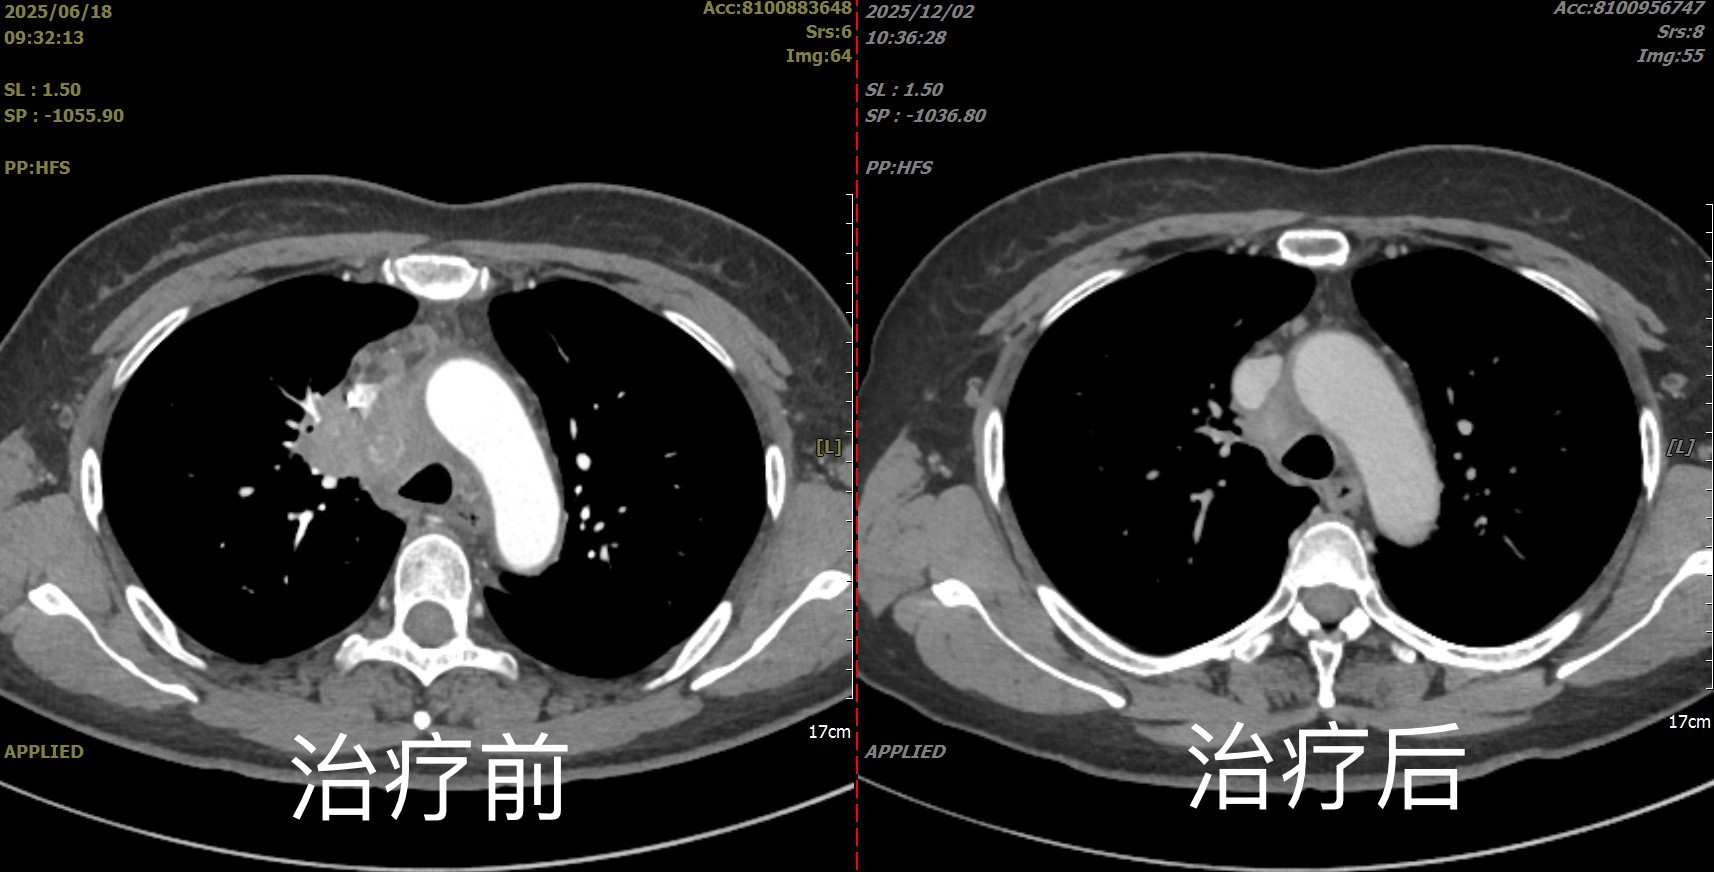

病例二:罕见病明确诊断,解开多年谜团

一位中年女性,持续低热、咳嗽伴纵隔淋巴结肿大多年,辗转多家医院未能确诊,曾疑诊淋巴瘤或结核,但治疗无效。患者来我院后,我们为其进行了超声支气管镜引导下纵隔淋巴结活检。获取的标本量足且质量高,病理结合特殊染色及基因检测,最终确诊为一种罕见的肺结节病。明确诊断后,调整治疗方案,患者症状得到快速缓解。此病例彰显了该技术在诊断复杂、罕见肺部疾病方面的独特价值。